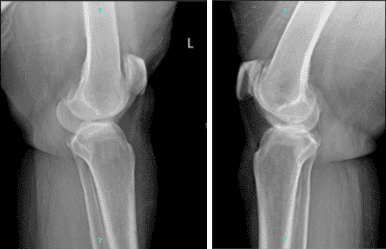

La paciente también trajo y presentó los resultados de radiografías de ambas rodillas. En el lado izquierdo, hay cambios degenerativos osteoartríticos leves. No hay fracturas agudas. Sin embargo, en el lado derecho, hay cambios degenerativos osteoartríticos moderados. Derrame articular. No hay fracturas.

Radiografía completa de la rótula de rodilla izquierda y derecha